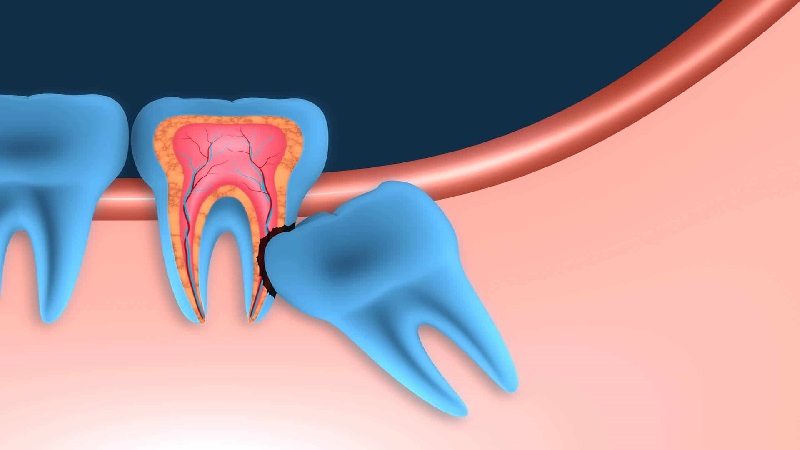

به سه دندان انتهایی و طرفی در هر فک دندان های آسیاب (یا دندان های آسیای بزرگ) گفته می شود. به سومین و انتهایی ترین این دندان ها نیز دندان عقل گفته می شود. این دندان در بسیاری از افراد به صورت غیر طبیعی رشد می کند و نه تنها باعث وارد شدن آسیب به سایر دندان های مجاورش میشود بلکه قادر است به بافت لثه و عروق حساس اطراف آن نیز آسیب بزند. این دندانها معمولا دیرتر از دندان های دیگر جوانه می زنند. سن جوانه زدن و بیرون افتان آن ها از لثه ها معمولا بین سنین 17 تا 12 سالگی است. در برخی شرایط ما مجبور هستیم که این دندان ها را به موقع بکشیم.

به غیر از آسیب دیدگی استخوان فک و باف لثه علائمی وجود دارد که نشان می دهد شما نیازمند کشیدن این دندان هستید. برای مثال ازدحام و کراودینگ دندان ها و عفونت داخل دهان دو علت مهم کشیدن دندان عقل بالا یا پایین به شمار می روند.

پیشگیری از آسیب دیدگی ساختارهای مجاور

در صورتی که باقی ماندند این دندان در داخل دهان شما تهدیدی برای سلامتیتان باشد، به منظور جلوگیری از شرایطی مانند ازدحام دندان ها، درد، آسیب دیدگی اعصاب و استخوان های فک و همچنین حفره ها دندانپزشک دندان انتهایی شما را می کشد.